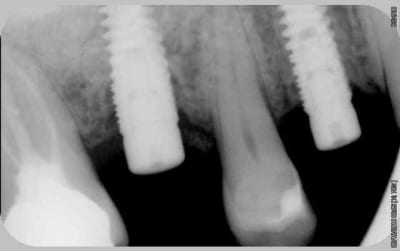

cas d'un axiom avec perte crestale et mise en charge en septembre voila l'évolution dans le temps la suite dans six mois

--

Une belle cratérisation!!!!